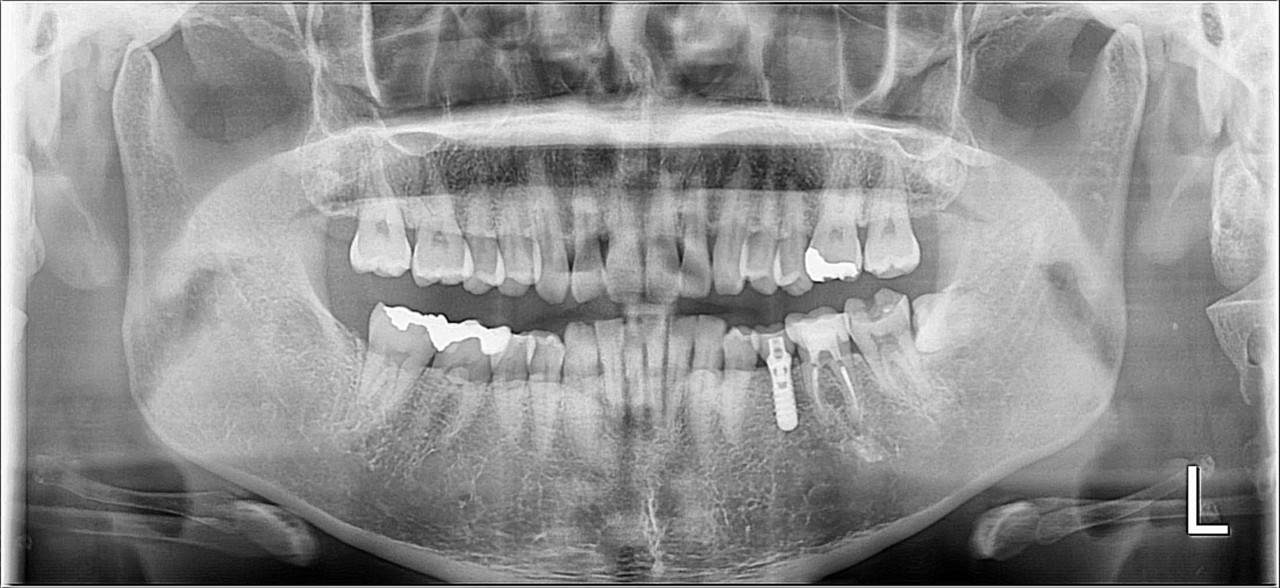

①パノラマ

パノラマは歯列矯正以外の治療でも必須のレントゲンです

事前に撮影することで

虫歯や歯周病、根の状態、顎関節、親知らずや上顎洞(副鼻腔)

安全に治療できるか、事前にやっておくことはないか

をチェックしています

矯正歯科にかかわらず、どこの医院でも撮影している

とても重要なレントゲンです